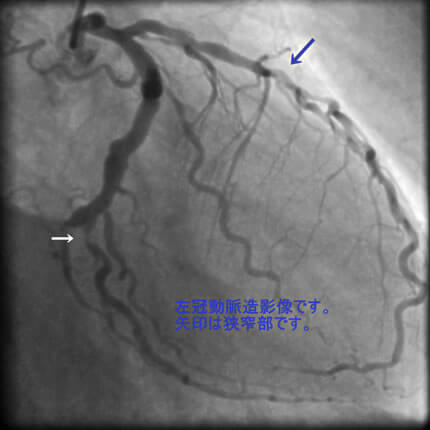

図1-2 左冠動脈造影像

よく解らないと思いますが、冠動脈に多数の狭窄があることと冠動脈が「こぶ状変化(医学用語で瘤状変化)」を生じているのが解ると思います。